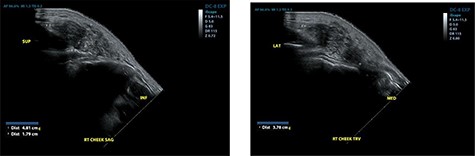

Ultrasound examination revealed a heterogenous lesion measuring 2.9 × 2.3 × 1.4 cm, with associated non-specific ipsilateral Level II cervical lymph nodes (Fig. 1). Haematological test results showed a leukocyte count of 8.47 × 109/l with an eosinophil rate of 17.4% (normal range is 1–5%) and normal renal function.

Ultrasound examination demonstrating a heterogenous lesion measuring 2.9 × 2.3 × 1.4 cm mass.